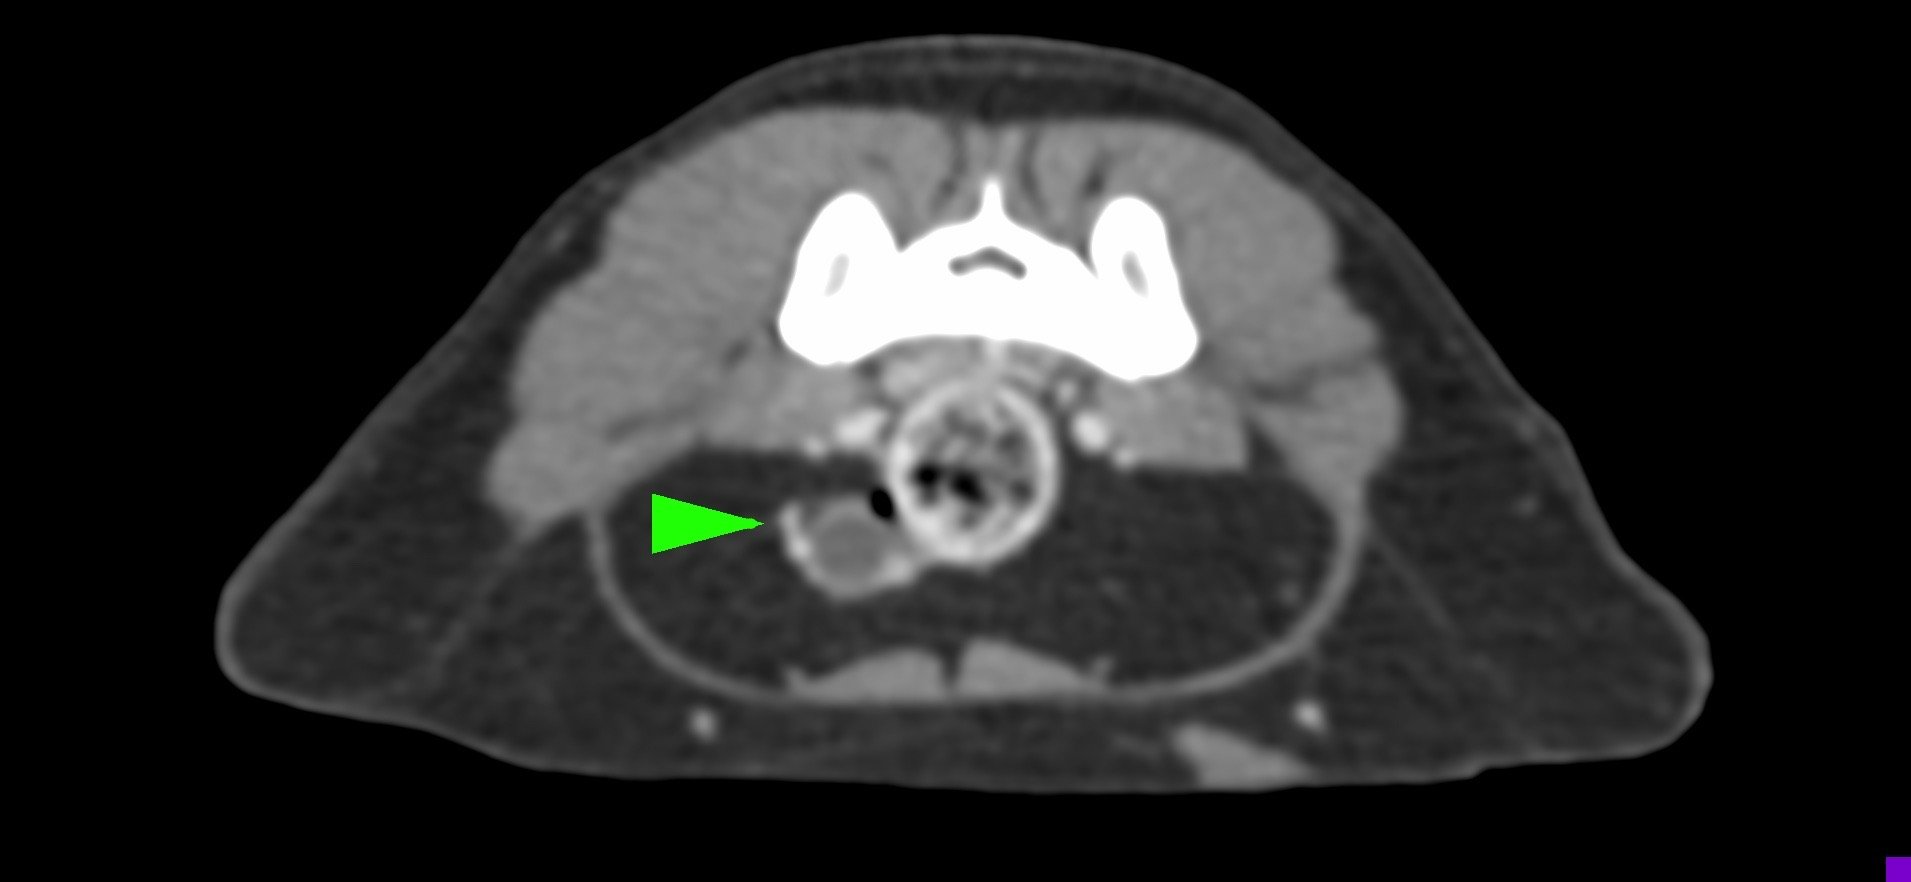

小花是一隻一歲多的母貓,半年前曾在其他醫院做過絕育手術,但手術當下卻只找到單側的子宮卵巢,且在這半年當中仍然反反覆覆地發情,讓飼主十分擔心,於是來到築心尋求治療。在了解小花的狀況後,我們為小花安排了電腦斷層掃描,並在腹腔的左側發現了疑似殘存的卵巢影像(見圖示),接著,在影像定位的協助下順利開腹取出殘存的卵巢和發育異常子宮角,而在殘存的子宮內已然形成了子宮蓄膿。